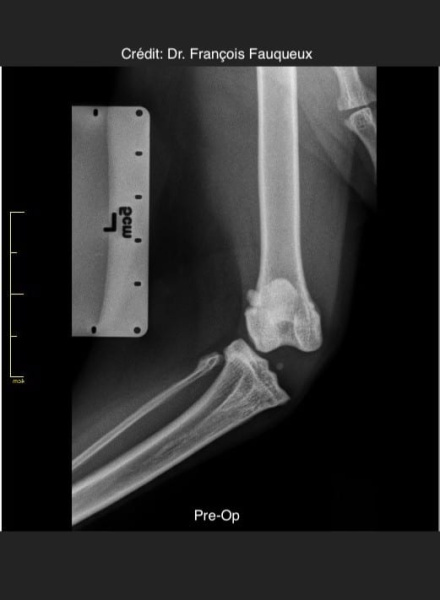

Radiologické snímky